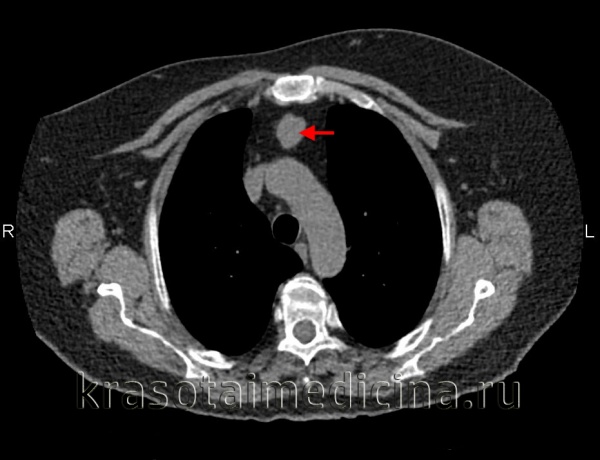

Наиболее грозным осложнением кист средостения служит так называемый синдром медиастинальной компрессии, частота которого колеблется от 27 до 39%. Сюда может входить компрессия дыхательных путей, синдром верхней полой вены (СВПВ), сдавление пищевода, сердца, возвратного нерва.

При компрессии дыхательных путей развивается стридорозное дыхание, одышка, дыхательная недостаточность. Синдром ВПВ проявляется цианозом кожи лица, видимых слизистых оболочек, шеи, верхних конечностей и грудной клетки; отечностью мягких тканей этой зоны; расширением и напряжением вен шеи; повышением давления в системе ВПВ. Сдавление кистами различных структур средостения может сопровождаться дисфагией, дисфункцией надгортанника, дисфонией, компрессией и дислокацией сердца.

Компрессия венозных стволов, прежде всего, проявляется так называемым синдромом верхней полой вены (СВПВ), при котором нарушается отток венозной крови от головы и верхней половины туловища. Синдром ВПВ характеризуется тяжестью и шумом в голове, головной болью, болями в груди, одышкой, синюшностью и отечностью лица и грудной клетки, набуханием вен шеи, повышением центрального венозного давления. В случае сдавления трахеи и бронхов возникают кашель, одышка, стридорозное дыхание; возвратного гортанного нерва - дисфония; пищевода – дисфагия.